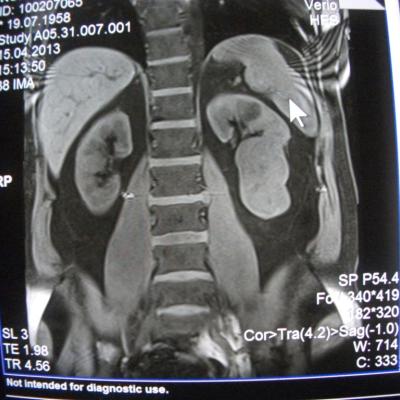

такое заключение: Левая почка: расположена обычно, увеличена, общими размерами около 13х5,5см. В области средней и нижней трети почки определяется объёмное образование неправильной формы, деформирующее наружный контур почки, распространяющиеся с чашечно-лоханочную систему. Опухоль имеет четкие неровные бугристые контуры с наличием псевдокапсулы, неоднородной структуры с признаками распада, максимальными размерами около 78,7х47х48мм

Вопрос такой: можно ли обойтись без удаления почки, удалив только опухоль.

Технически можно. Но практически - лучше нефрэктомия.